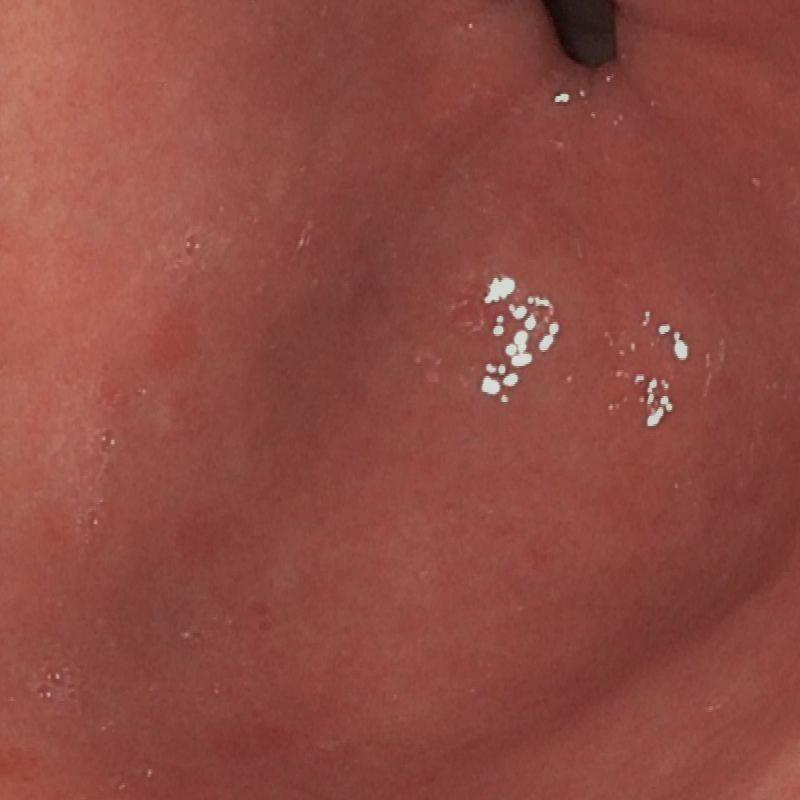

To validate the effectiveness of each module introduced in the proposed network, we conducted an ablation study involving the following two experiments: 1) Without Cross-attention: We removed cross-attention from the model. 2) Without SSM: We removed SSM from the model using a conventional linear layer in its place. Table 2 and Figure 3 compares our method with two ablation studies.

| (a) Input | (b) w/o Cross-attention | (c) w/o SSM | (e) Ours | (f) GT |